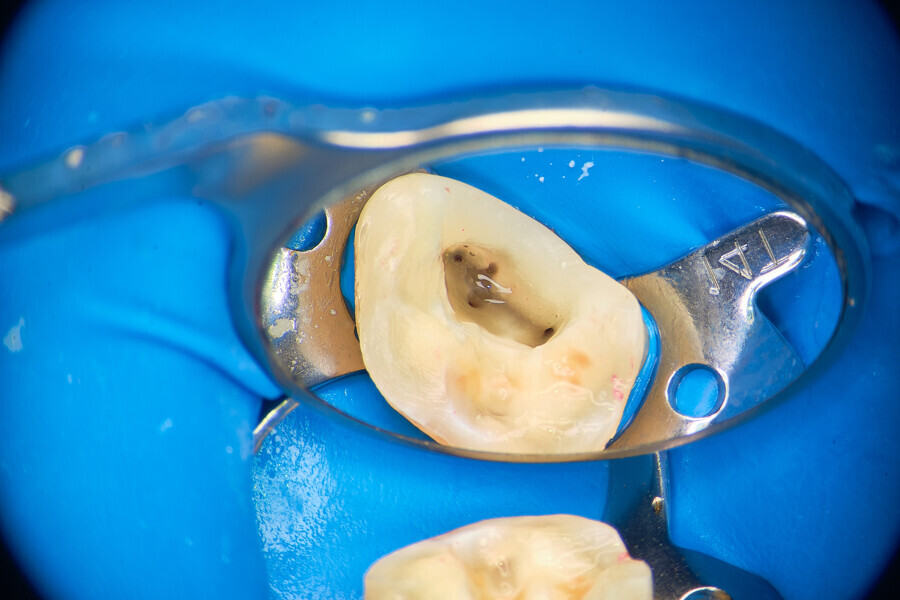

Fig.: 19

Case 2

A 56-year-old patient was referred to our clinic for endodontic treatment of tooth #15. The initial radiograph showed a complex anatomy with abrupt curvatures (Fig. 19). In such cases, our main goal is to avoid breaking the instrument. The in–out technique is a good choice in these situations too. After isolation, the access cavity was created (Fig. 20). Owing to abrupt curvatures in both canals located, a glide path was achieved with manual ISO #8, 10 and 12 K-files (VDW; Fig. 21). During manual instrumentation, small adjustments to the access cavity were made with an ultrasonic tip (Fig. 22).